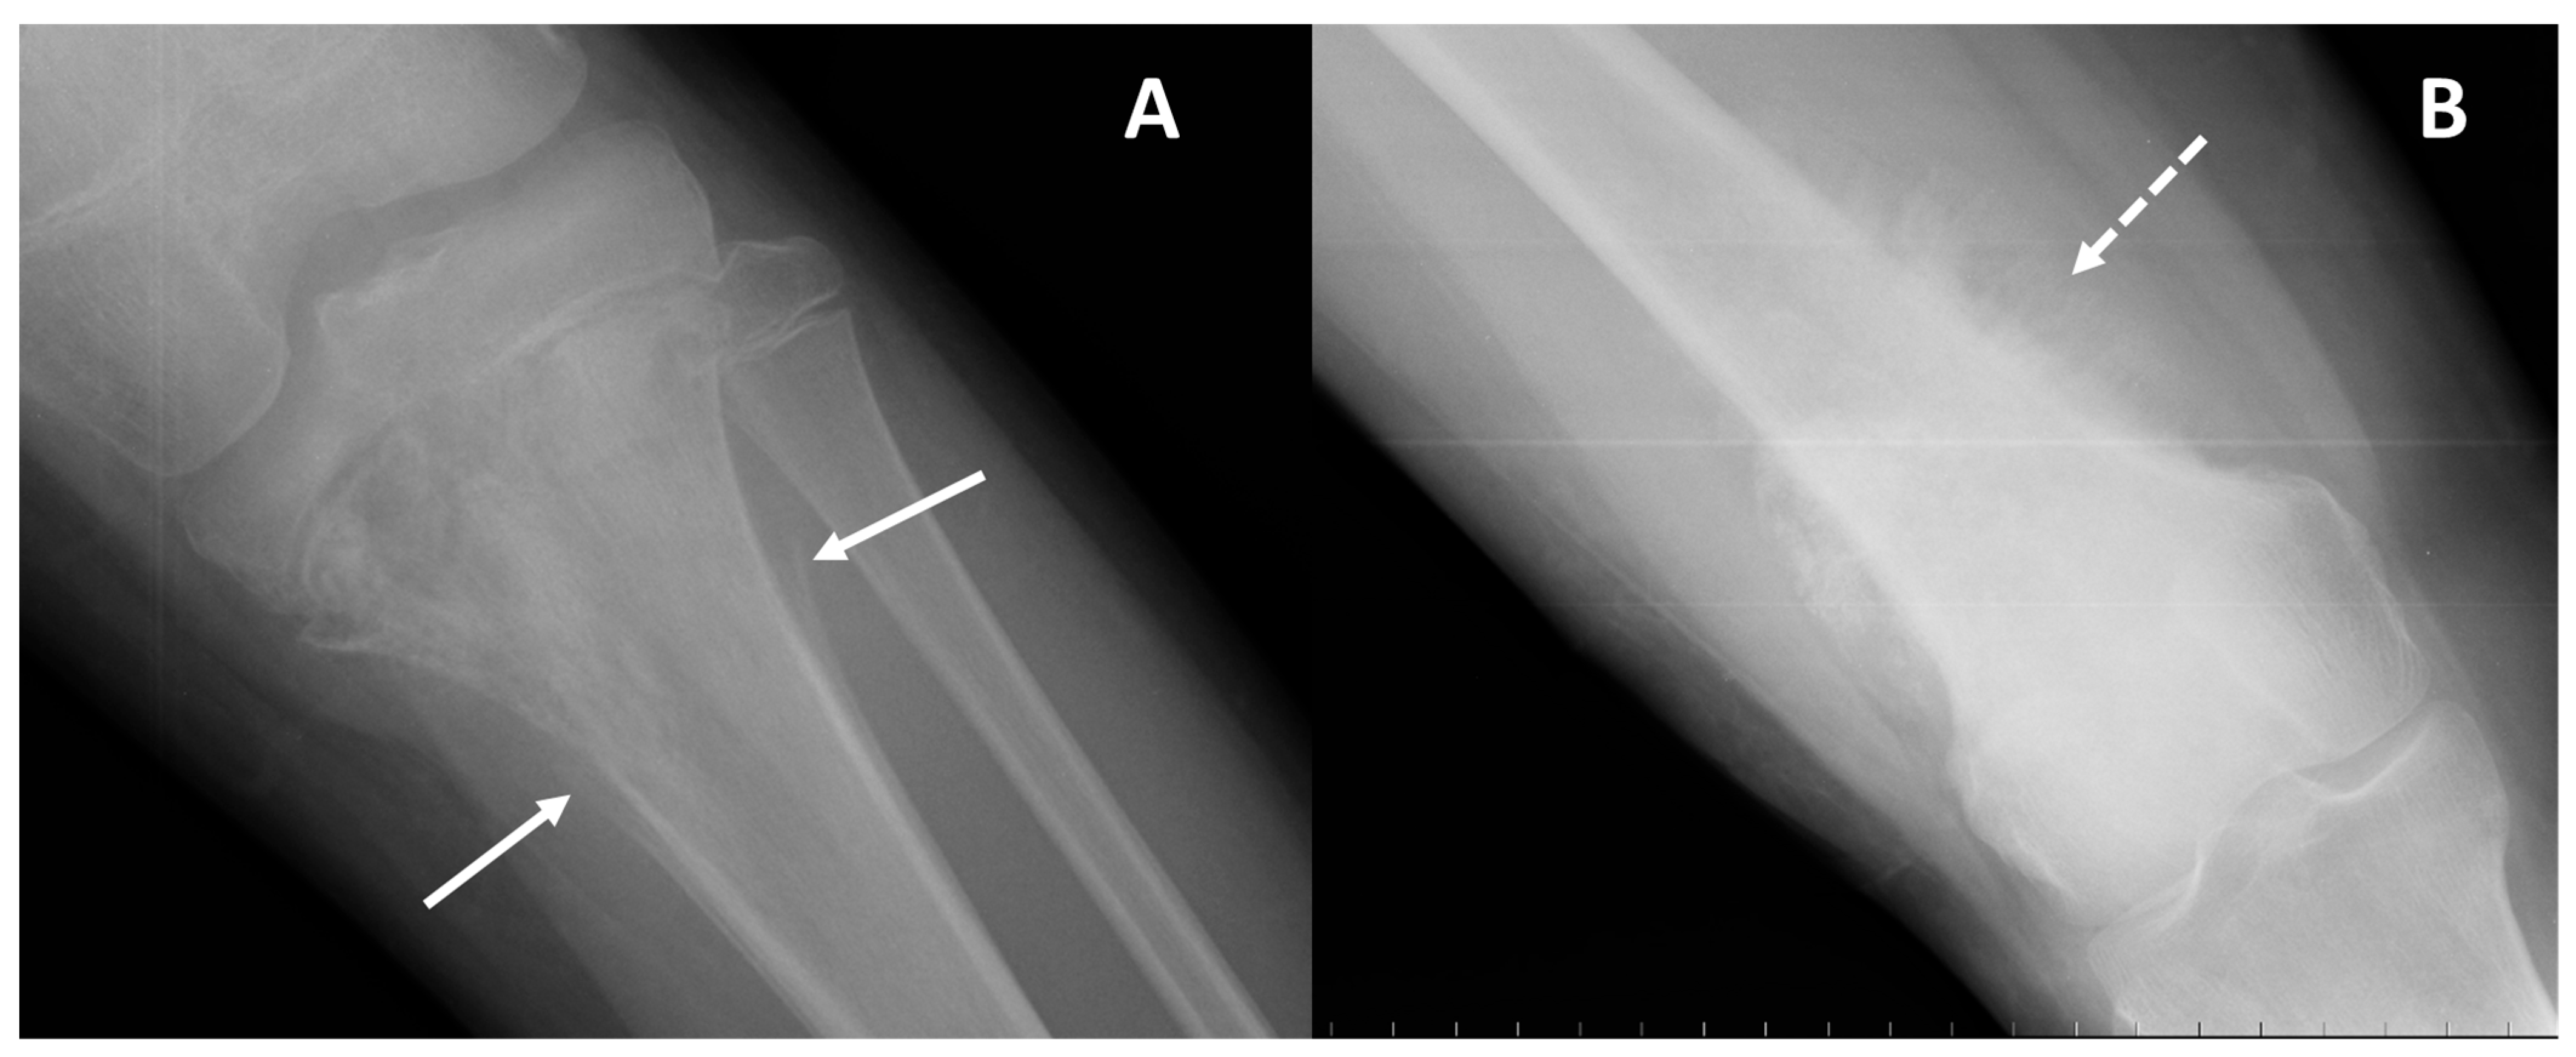

| Conventional osteosarcoma | Mixed (lytic and sclerotic) or completely eburneous | Sunburst, Codman triangle, other irregular/aggressive types | Soft-tissue components frequently displayed |

| Telangiectatic | Purely osteolytic | None or thin regular | Multicystic pattern with fluid–fluid levels and solid components on MRI |